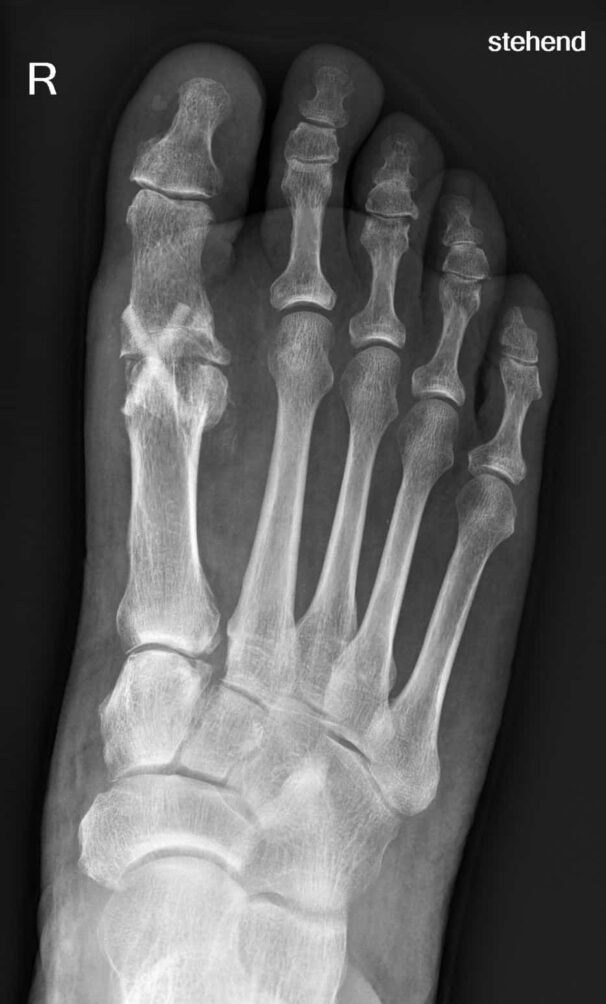

During production, the bone is first sterilized to ensure that no rejection reactions or disease transmission occur. A human bone matrix remains which is inserted into the human body in screw form. There it is immediately recognized as the body’s own – supplied with blood and integrated into the bone. After only six weeks, it has grown through with the body’s own tissue, and after approximately one year, it has healed completely into the patient’s bone and can no longer be seen in X-rays.

Patients who receive Shark Screw benefit from a maximum likelihood that the bone fragments will grow together and the bone screw will be converted into the patient’s own bone. This saves them the need for a second operation to remove the metal. Shark Screw can be used for fractures, deformities – such as hallux valgus – or joint wear or osteoarthritis.